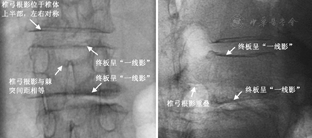

采用"一线影"基准定位法,在穿刺操作前调整X线球管的投照方向,使骨折椎体的终板呈"一线影",即骨折椎体的上/下终板在正侧位X线透视像上呈一直线,并且两侧的椎弓根影在正位透视像上以棘突为中心的对称分布,在侧位透视像上完全重叠(图1)。穿刺前对骨折椎体进行透视下定位,确定合适的穿刺点和穿刺路径,避免X线投照偏差造成穿刺失败。